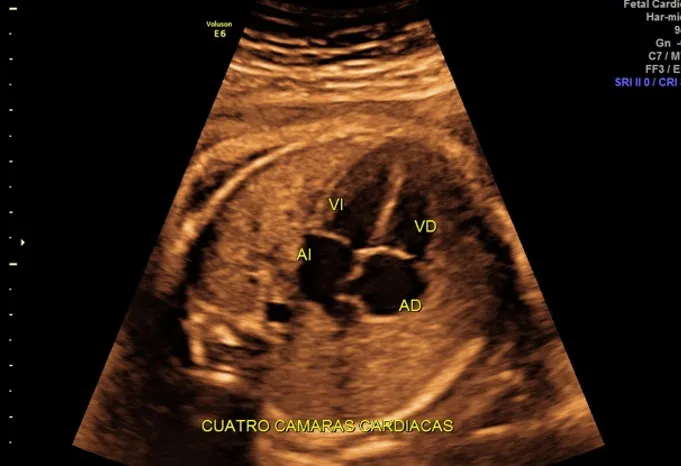

En este estudio de primer trimestre se realiza una evaluación estructural detallada de bebé de cabeza a pies para descartar malformaciones mayores y revisar que todos los órganos vayan desarrollándose de manera normal, también se buscan cuatro marcadores en bebé que son llamados genéticos (translucencia nucal, hueso nasal, ductus venoso y flujo tricuspídeo), se sabe que en bebés sanos estos marcadores están presentes y deben ser normales, los bebés que los tienen alterados tienen mayor riesgo de alteraciones genéticas como síndrome de Down, como parte de este estudio se toma la presión del útero y en combinación con otros datos como peso, presión arterial del brazo, etc se puede calcular el riesgo de preeclampsia (presión alta al final del embarazo).

- Realizar una evaluación estructural temprana detalla para descartar malformaciones mayores.